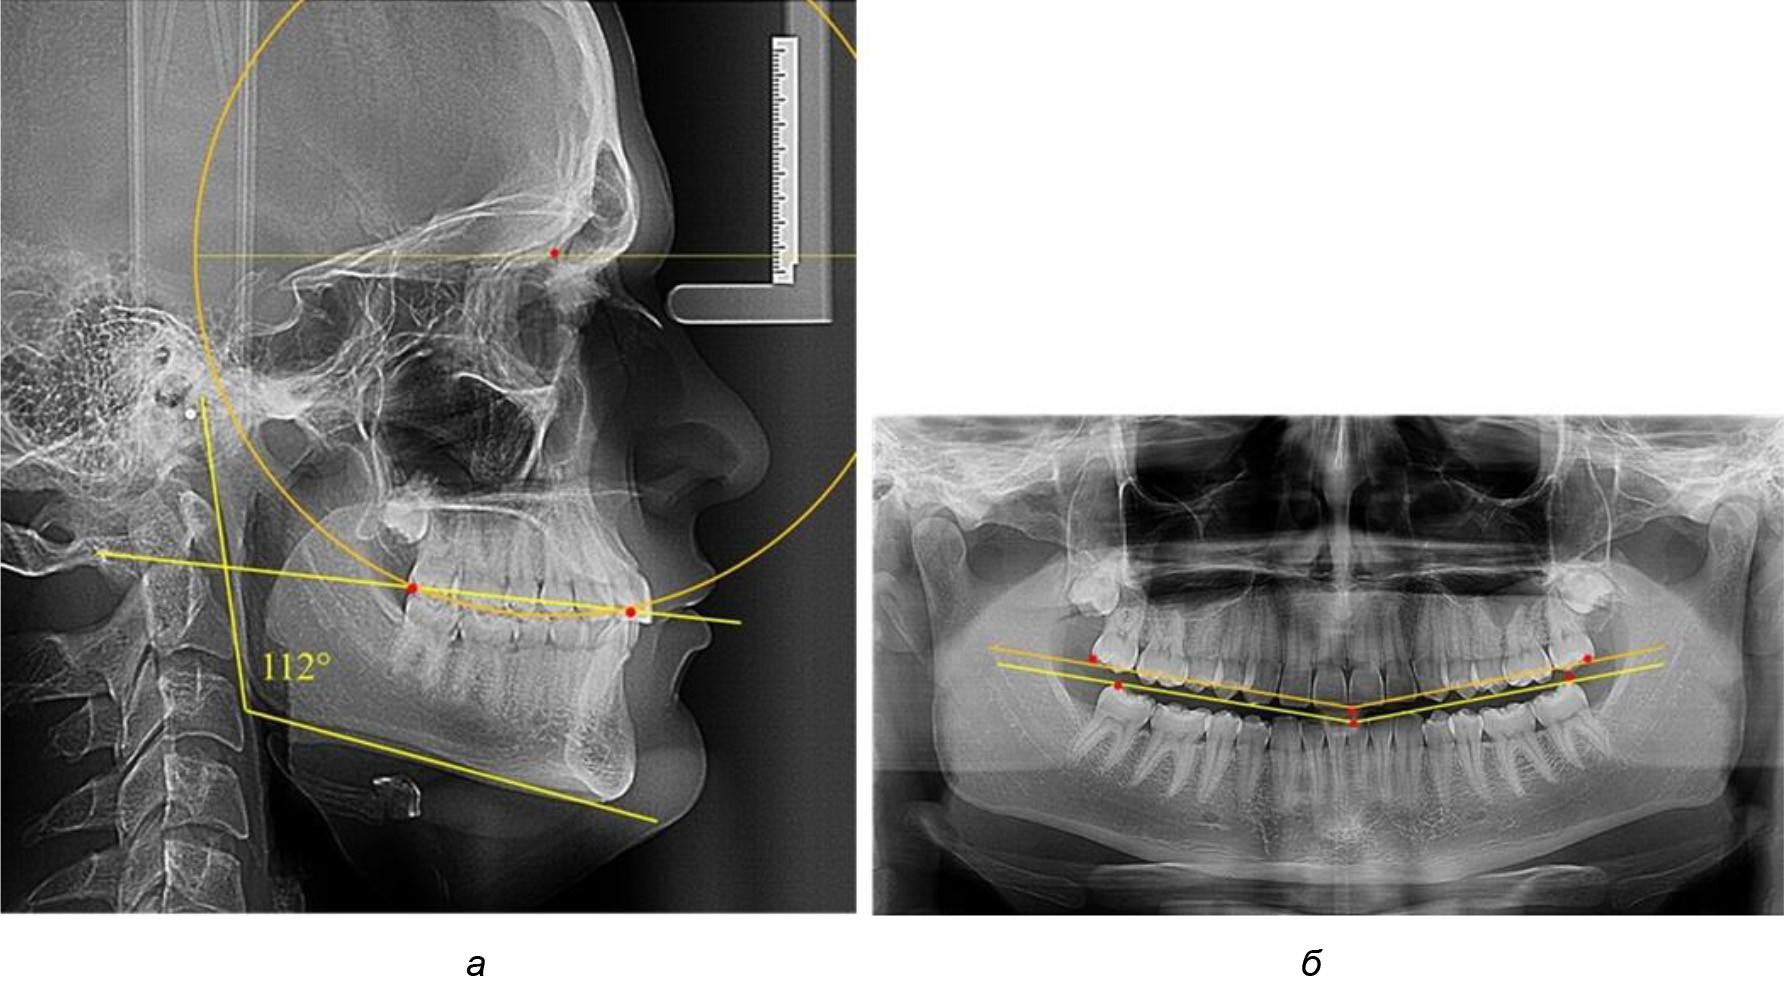

При анализе латеральных ТРГ устанавливали реперный окклюзионные точки в переднем и боковом отделе. Передняя точка устанавливалась на режущем крае нижнего медиального резца, которую в клинике ортодонтии обозначают как vPOcP. Дистальная точка второго нижнего моляра обозначалась как hPOcP. Измеряли расстояние между окклюзионными точками, что определяло сагиттальный размер окклюзионной линии. Использование программ PowerPoint позволило проводить окружность, проходящую по линии смыкания зубов через окклюзионные точки. Измеряли радиус окружности. Учитывая вариабельность размеров окклюзионной линии и радиуса окружности, определяли относительный показатель через отношение радиуса круга к длине сагиттального размера окклюзионной линии. Глубину окклюзионной кривой измеряли от точки наибольшей выпуклости до окклюзионной линии (рис. 1). На ортопантомограмме (ОПТГ) также соединяли окклюзионные точки правой и левой стороны и измеряли глубину окклюзионной кривой от точки наибольшей выпуклости до окклюзионной прямой линии. Результаты глубины кривой Spee сравнивали по данным ТРГ и ОПТГ.

Рис. 1. Метод определения кривой Spee на ТРГ (а) и на ОПТГ (б)